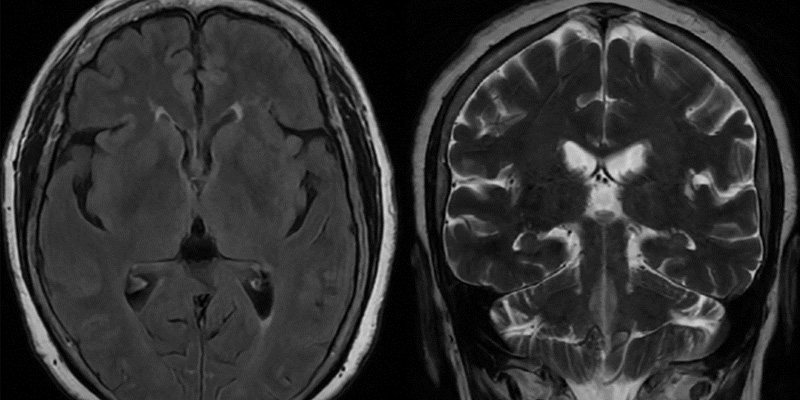

Chẩn đoán hình ảnh (MRI, CT, PET-CT)

MRI não

Đây là tiêu chuẩn vàng trong phát hiện ung thư não, cho thấy:

- Kích thước, vị trí và ranh giới khối u

- Mức độ xâm lấn

- Phù não xung quanh